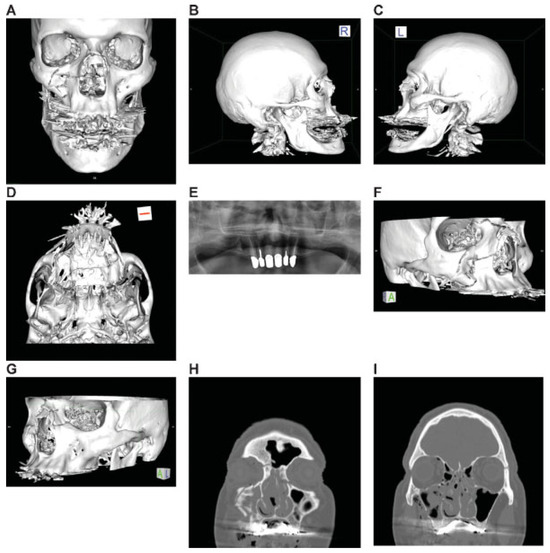

Figure 6.

Asymmetric Le Fort Level midface fracture. Three-dimensional (3D) computed tomographic (CT) scans— (A) frontal view, (B) lateral view right, (C) lateral view left, (D) basal view—mandible removed; (E) panoramic X-ray–OPT; (F, G) 3D CT scans—oblique views, right,left (H, I) coronal CT scans. (J–M) axial CT scans; (N) sagittal CT scans—at lateral lamina of pterygoid process right, (O) at medial lamina of pterygoid process right, (P) at medial lamina of pterygoid process left, (Q) at lateral lamina of pterygoid process left, and (R) at lateral orbital rim left. (S) Level 3 Code : 92 I0i.L0.Pt0.Oim.U1m.Omil.Pt0.L0.Z0, Orbit (right): R(im).W1(im)2(i), Orbit (left): R(lm).W1(lim)2(i), This case example CMTR-92-101 is made available electronically for viewing using the AOCOIAC software at www.aocmf.org/classification. Narrative description: Le Fort analogous midface fracture (central right—types I and II/centrolateral left types I and III). Unilateral NOE fracture right—large fragments, multifragmentation of facial antral wall right, nasal skeletal fracture (multifragmanted and displaced) involving both frontonasal processes and nasal bones not reaching cranially to the nasofrontal suture. Partial Dentition (FDI): Lack of 18–14; 24–28. Maxillary alveolar process atrophy: moderate. Pterygoids: bilateral incomplete horizontal fractures, no pterygomaxillary disjunction, i.e., vertical separation. Displacement: No retrodisplacement of both maxillae, no displacement of the Le Fort I and III fragments left, multifragmentation facial antral wall right, minor displacement of frontonasal fragment right. Internal orbits: Involvement confined to anterior and midorbit sections: right, medial and inferior walls, left medial, inferior and lateral walls.